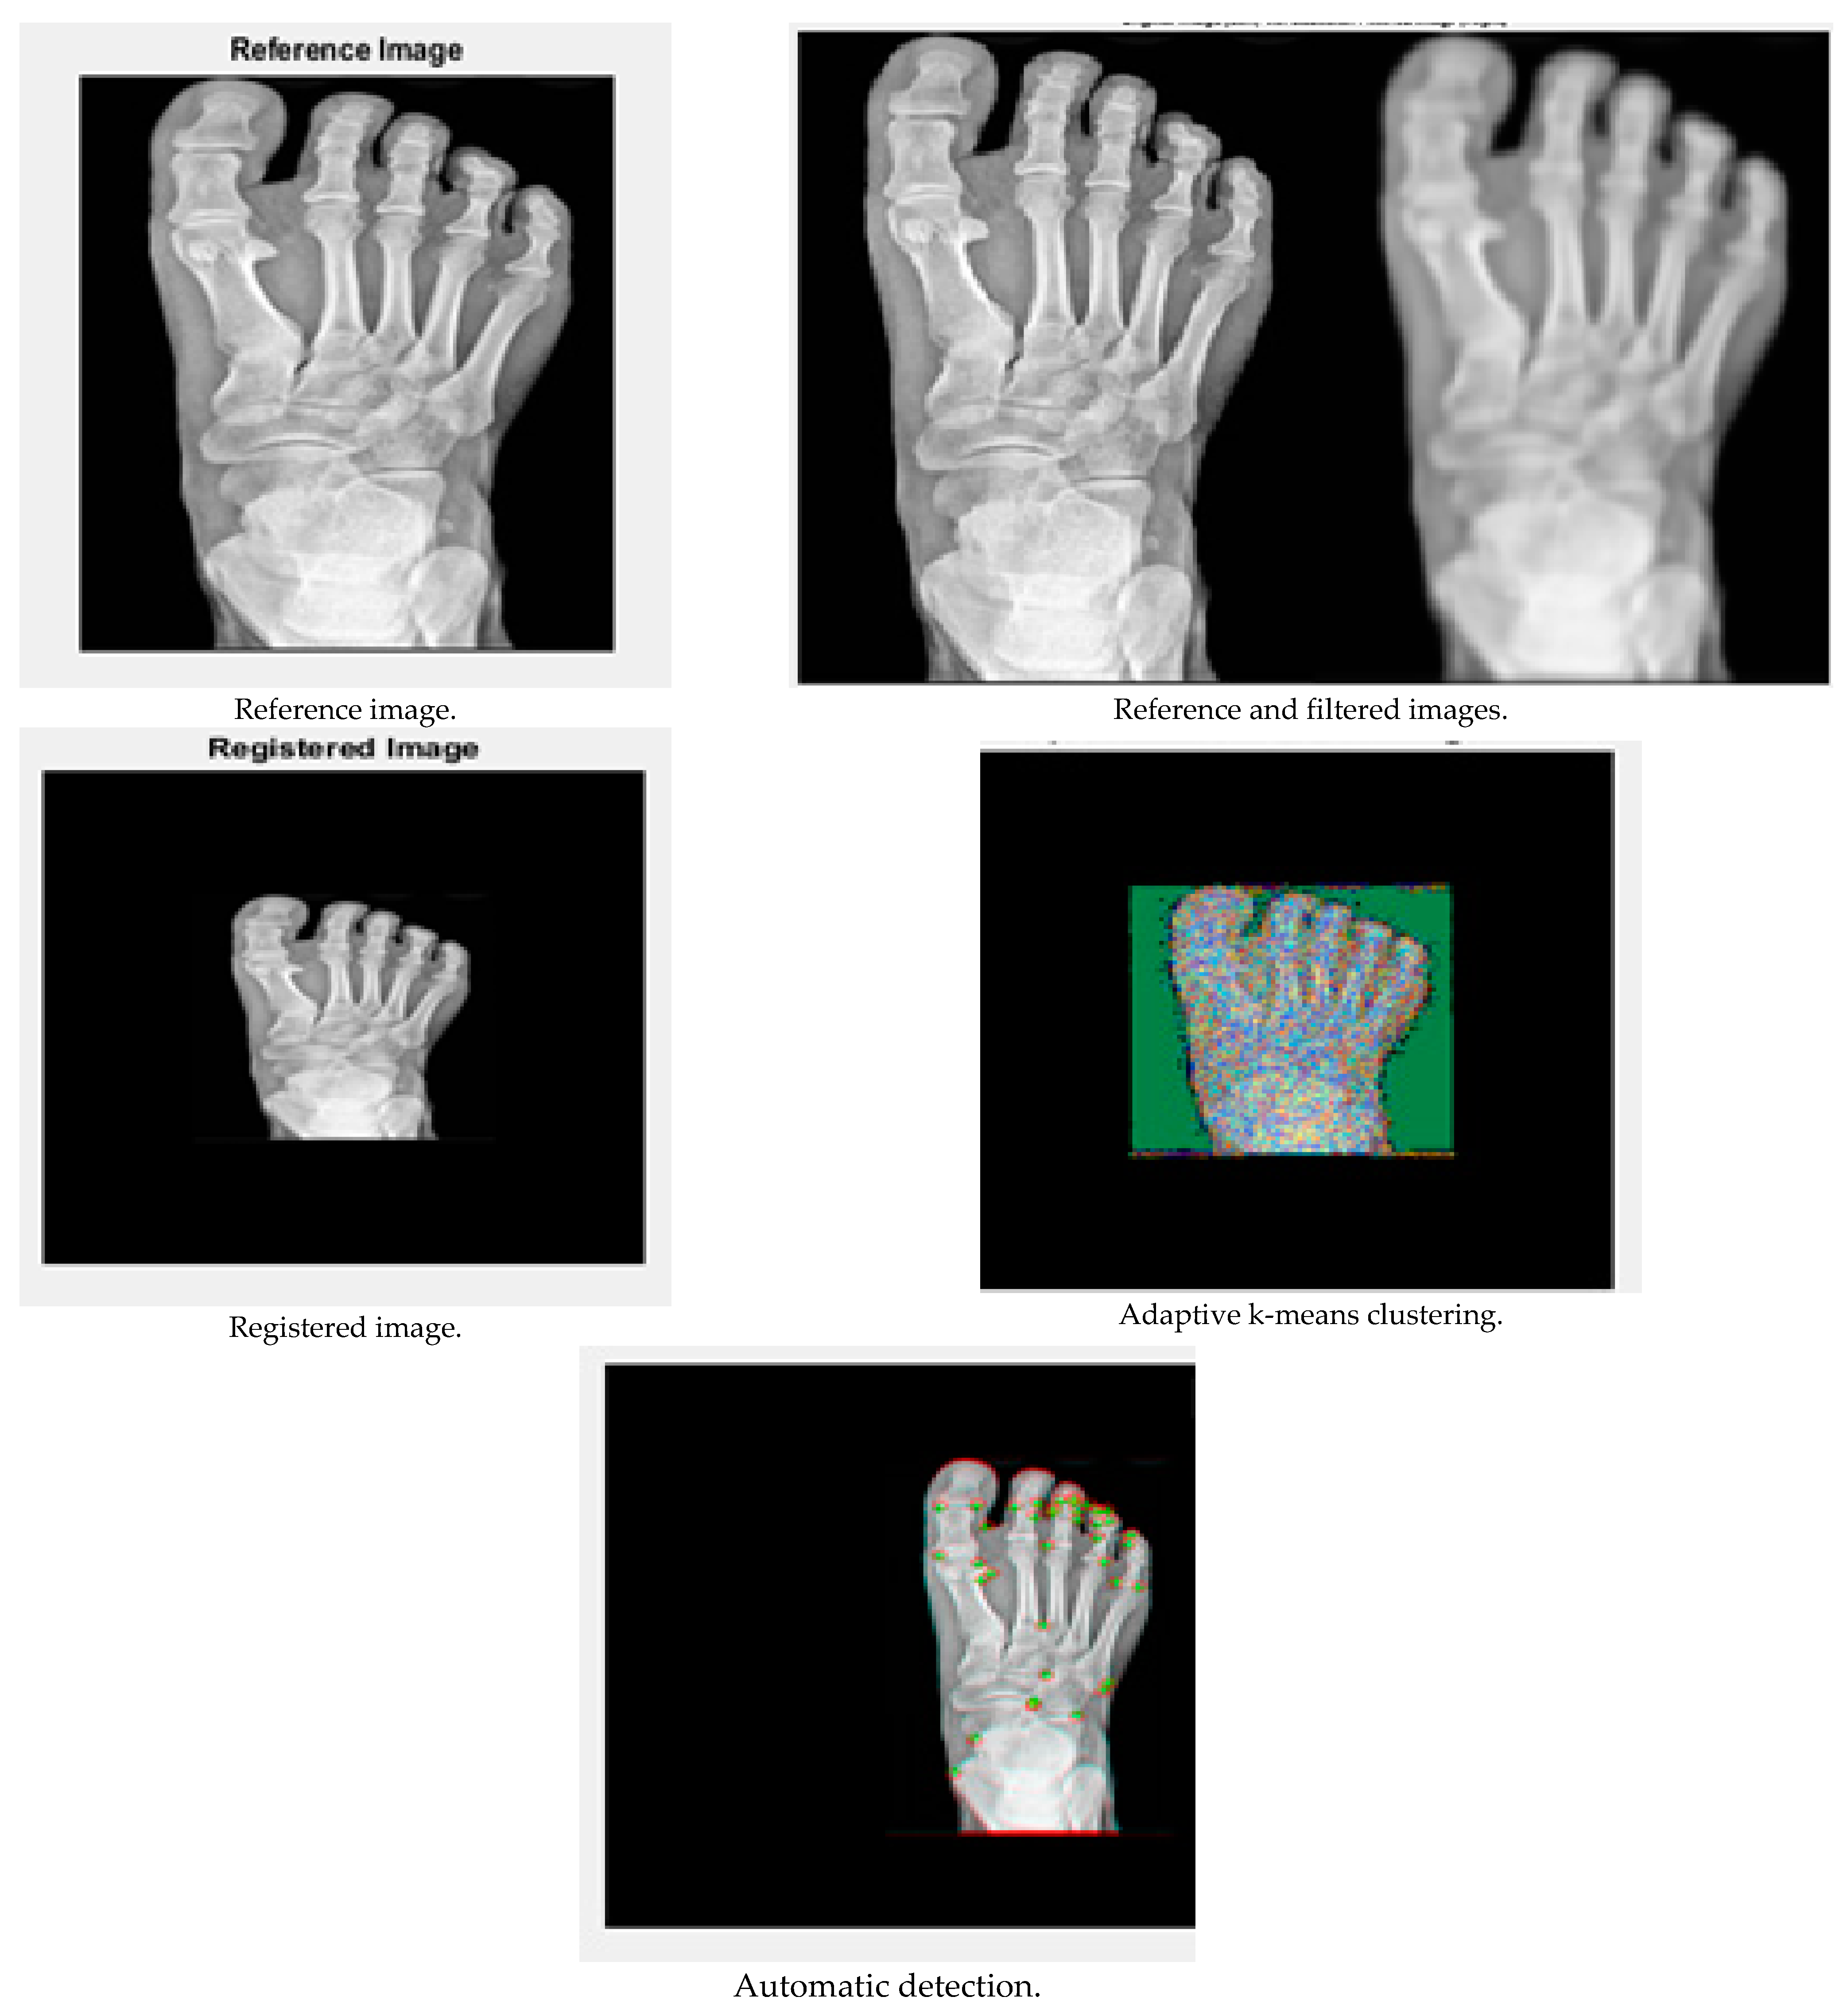

The performance of the results is demonstrated in this Results and Discussion section. The input X-ray images were taken from the website kaggle, and the results were obtained using MATLAB R2019a. The results are shown in Figure 3 and Figure 4:

Figure 3.

Performance analysis of image 1.

Figure 4.

Performance analysis of image 2.